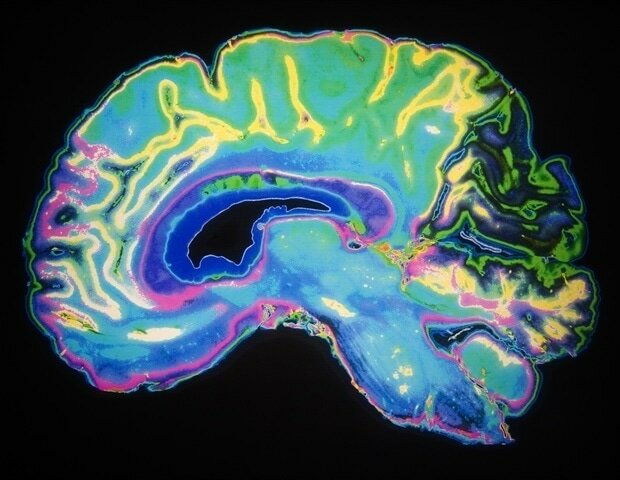

عامل مختل کننده حافظه و یادگیری

عامل مختل کننده حافظه و یادگیریبر اساس تحقیقات دانشگاه لستر انگلستان مشخص شد چه عاملی عملکردهای شناختی مانند حافظه و یادگیری را با افزایش سن دچار اختلال می‌کند.

به گزارش ایسنا و به نقل از نیوز، نتایج این تحقیقات نشان می‌دهد که میزان کلسیم، نقش مهمی در عملکرد سلول‌های خاص در مغز دارد.

با افزایش سن حافظه انسان کاهش می‌یابد و یادگیری موارد جدید در سن بالا سخت‌تر می‌شود. بسیاری از افراد تصور می‌کنند علت این کاهش یادگیری به دلیل از بین رفتن تدریجی سلول‌های مغزی است، اما علت اصلی آن کاهش سلول‌های مغزی نیست.

علت این مورد واکنش در سیناپس‌ها است که اتصالات الکتروشیمیایی بین سلول‌های عصبی و مولکول‌های انتقال‌دهنده عصب در ایجاد شبکه سیستم عصبی مرکزی است.

پروفسور نیک هارتل از گروه علوم اعصاب­- روانشناسی و رفتار دانشگاه لستر میزان کلسیم موجود در هیپوکامپ، بخشی از مغز که در یادگیری و حافظه درگیر است را مورد بررسی قرار داد.